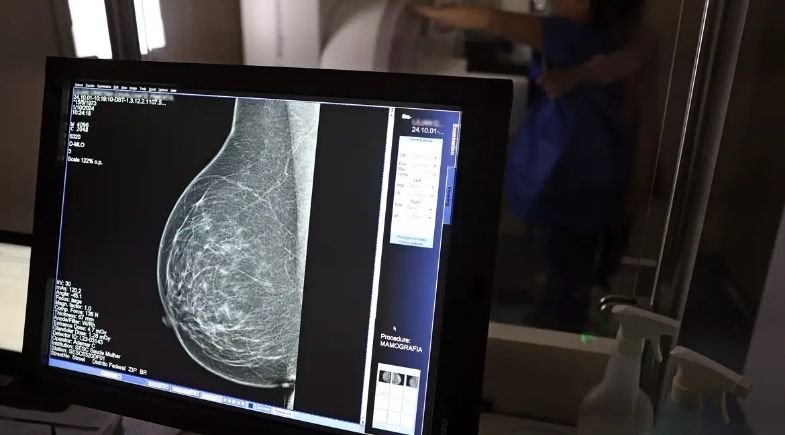

Câncer de mama: uma em cada três pacientes tem menos de 50 anos | Foto: José Cruz/Agência Brasil

Dados do Painel Oncologia Brasil revelam que mais de 108 mil mulheres com menos de 50 anos foram diagnosticadas com câncer de mama entre 2018 e 2023. O levantamento, analisado pelo Colégio Brasileiro de Radiologia e Diagnóstico por Imagem (CBR), aponta que esse grupo representa um terço dos casos registrados no país nesse período.

O número levanta um alerta sobre a atual política de rastreamento do Sistema Único de Saúde (SUS), que prioriza a mamografia para mulheres entre 50 e 69 anos. Para o CBR, os dados demonstram a necessidade urgente de ampliar o acesso ao exame para mulheres mais jovens, que vêm sendo afetadas pela doença de forma crescente.